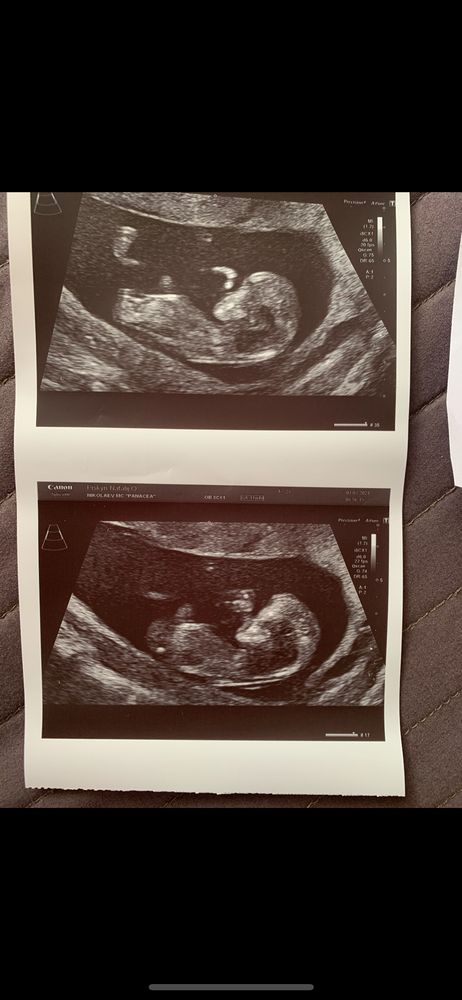

Мне по этому фото с первого скрининга все на ББ написали, что похоже на девочку) в итоге в 15 недель уже отчетливо видно было, что там парень сидит 😃 Изображение

Ваши фото очень похожи на наши (лицо) :) у нас девочка.

05.09.2021